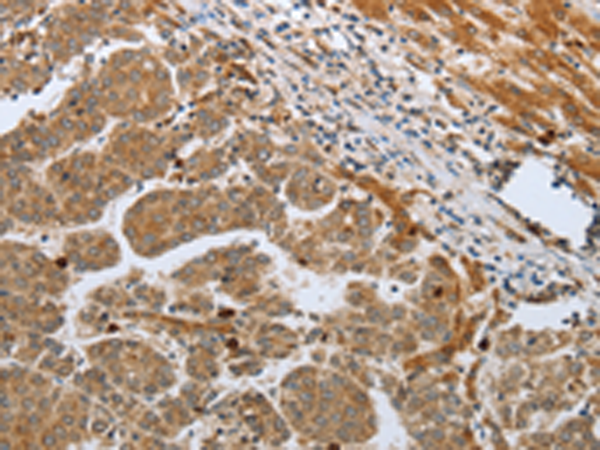

分类: 科研抗体货号: P10727别名: FAD, FACD, FAD1, GLM3, BRCC2, FANCB, FANCD, PNCA2, FANCD1, BROVCA2应用: IHC反应种属: Human